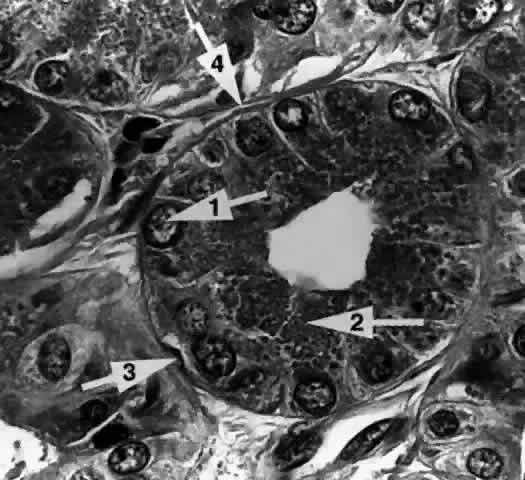

The Acinar Unit (Fig. 13)

Fig. 13. The acinar unit is composed of a central lumen, a continuous inner epithelial layer of secretory cells, and an interrupted outer layer of myoepithelial cells. (H & E, original magnification × 250; Courtesy of Ralph Eagle, MD, Philadelphia, PA)

Each lobule consists of a complicated grape-like (Fig. 14) arrangement of acini. Each acinar unit (Fig. 15) consists of a central lumen, a continuous inner layer of columnar secretory epithelial cells, and a surrounding interrupted outer layer of irregularly shaped myoepithelial (basket) cells.9

Fig. 15. The acinar unit. The columnar secretory cell has a basally located nucleus (arrow 1). Zymogenic secretory granules (arrow 2) are seen in the midportion and apical cytoplasm. A myoepithelial cell (arrow 3) is interspersed between the secretory cell and the basement membrane (arrow 4). (H & E, original magnification × 250; Courtesy of Ralph Eagle, MD, Philadelphia, PA)

The acinar secretory cell typically has a basally located nucleus with one or two nucleoli, as seen with electron microscopy. The predominant structures in its cytoplasm are the numerous zymogenic secretory granules located mainly in the apical or midportions of the cell9 (see Fig. 15).

Myoepithelial cells (see Fig. 15) appear as flattened, stellate, or spindle-shaped cells interspersed in the basal part of the acinar wall, between the secretory cells and the basement membrane. They are characterized by the presence of cytoplasmic myofilaments. The myofilaments consist of actin-type filaments in a parallel fashion, in some areas resembling fusiform smooth muscle.9,11

A thick, often multilayered basement membrane (see Fig. 15) surrounds the outer surface of the acinus, separating it from the intralobular connective tissue. Collagen fibrils, capillaries, unmyelinated nerve fibers, fibroblasts, plasma cells, and lymphocytes can be found within this connective tissue. The plasma cells have been shown to produce IgA, an immunoglobulin typically elaborated at mucosal surfaces. Acetylcholinesterase activity has been found around the acini, particularly adjacent to the myoepithelial cells, suggesting that they are the primary neural target for parasympathetic activity.16,17